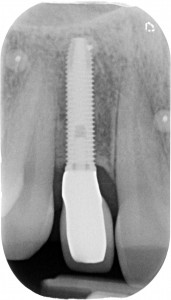

Sconosciuto-X-20151123-200312-XYHMH6ZQBS2X-4

senza tecniche di chirurgia avanzata?

Attenzione a non confondere: ho detto avanzata. Non invasiva.

Nel secondo, ad esempio, un ponte non è paragonabile alla soluzione ricostruttiva che ho attuato. Neanche lontanamente! Quindi è inutile dire

“il ponte sarebbe stato meno invasivo”

Perché il ponte non era la terapia giusta in questo caso! PUNTO! Avrebbe richiesto un sacrificio biologico drammatico in una ragazza di 28 anni e avrebbe portato ad un estetica diciamo “discutibile” vista la mancanza di volume rosa residuata dopo la rimozione dell’impianto infetto.